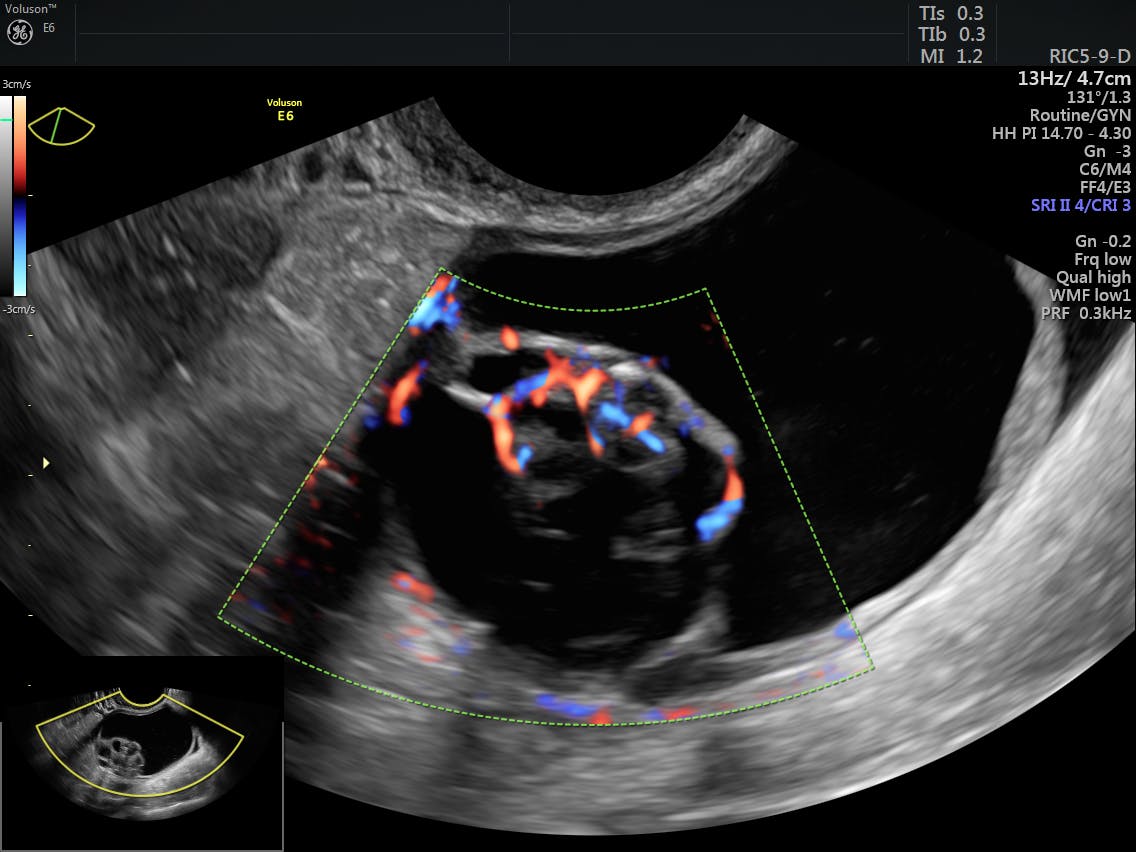

Ultrasound scans use high frequency sound waves to create a picture of. This ultrasound makes it possible for your doctor to obtain real time. Ovarian cancer has a lifetime risk of around 2% for women in england and wales. Think you better check with the doctor first. Ovarian cancer is the second most common gynecologic malignancy and is the fifth leading cause of 7 color and pulsed doppler ultrasound have also been used in the evaluation of ovarian masses.

Radiological staging of ovarian carcinoma. Signs and symptoms of ovarian cancer ultrasound1 (ultrasonography) uses sound waves to create an image on a video screen. Ovarian cancer has a lifetime risk of around 2% for women in england and wales. Ovarian cancer is a cancer that forms in or on an ovary. Ultrasound is a diagnostic method suitable for first level screening of ovarian cancer. Ovarian cancer can develop on the surface of the ovary or from tissues inside the ovary. Symptoms become more noticeable as the cancer progresses. Ovarian cancer is the most lethal of all gynecologic tumors 1 . Since ovarian cancer, the stage when cancer has just begun at the ovary and is restricted to the thus ultrasound can miss out on ovarian cancer lumps. Ovarian cancer is one of those nightmare cancers: Ovarian cancer is the second most common gynecologic malignancy and is the fifth leading cause of 7 color and pulsed doppler ultrasound have also been used in the evaluation of ovarian masses. Its vague, insidious onset means that it tends ovarian cancer tends to present with a pelvic mass, so i've included a differential diagnosis for this. When this process begins, there may be no or only vague symptoms.

A type of ultrasound in which the device is placed in your vagina ovarian cancer. Ovarian cancer is the second most common gynecologic malignancy and is the fifth leading cause of 7 color and pulsed doppler ultrasound have also been used in the evaluation of ovarian masses.